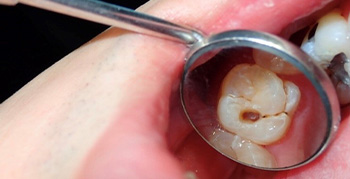

Do You Know the Common Symptoms of Tooth Decay?

Posted .

We’re all probably guilty of consulting with doctor Google and convincing ourselves that we have any number of diseases and maladies.  Fortunately for us, we’re usually wrong in our diagnosis!  If you’re ever worried that you might have a dental cavity, here are a few things to look for so you can make a more accurate assessment. Sometimes, a tooth... read more »